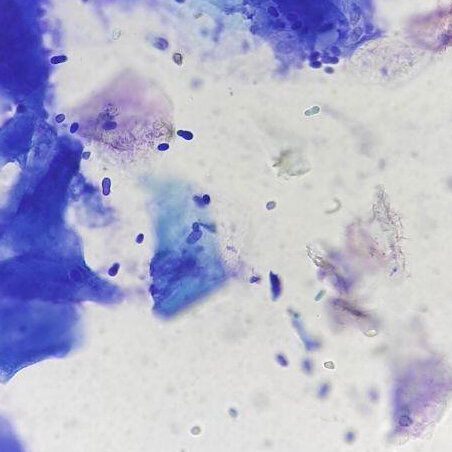

В качестве диагностического исследования для выявления повышенного количества грибов малассезия используются мазки-отпечатки с пораженной кожи и наружного слухового прохода, которые врач может изучить во время приема. Оценивая количество дрожжевых грибов в препаратах и сопоставляя это с внешним видом поражений, ветеринарный дерматолог может сделать выводы о том, являются ли дрожжевые грибки причиной воспаления.

Малассезиозный дерматит собак фото